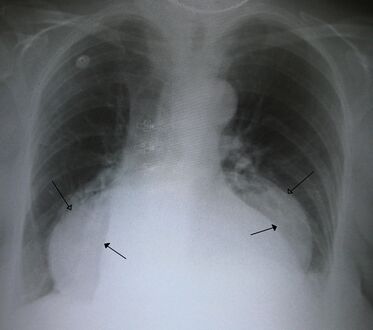

-

فتق حجابي كبير في صورة للصدر بالأشعة السينية، حيث يُميز بأسهم مفتوحة على النقيض من حدود القلب التي تتميز بأسهم مغلقة.

يتم تشخيص الفتق الحجابي هذا بشكل أساسي من خلال مستوى الهواء والسائل (الموضح بواسطة الأسهم).